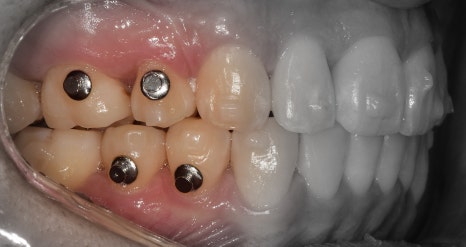

『발치 및 장치 부착, 인비절라인 진행』

표시를 해 둔, 갈고리처럼 생긴 것들은

Power arm 이라는 것들입니다.

이는, 치아들을 계획 했던 대로 정확히

이동을 시키게끔하는 보조수단으로 쓰입니다.

이후, 발치 공간이 조금씩 거의 다 폐쇄되면서

인비절라인 실버버튼을 부착시킵니다.

이것 또한, 보조도구입니다.

치열 전체를 덮는 인비절라인과 같이 맞물려서

정확한 치아의 위치 이동을 돕는 역할입니다.